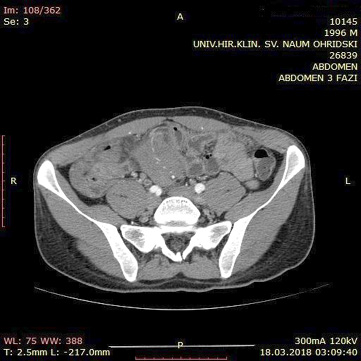

A contrast enhanced CT scan was indicated due to the palpable abdominal tumor and it revealed a formation that originates from the ileal mesentery involving the ileocolic artery and a part of the ileum with ileal wall thickening and partial obstruction (Figures 2, 3 and 4).